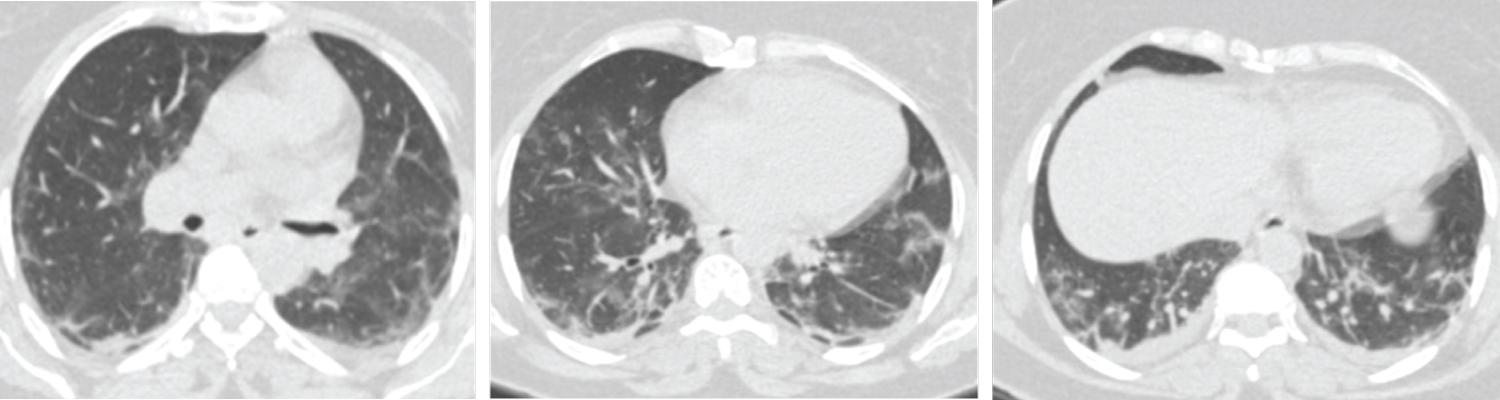

In addition, the age group was categorized into three groups: Those with less than 40 years of age; between 40 and 60 years and those above 60 years. There was significant correlation of CT severity score with increasing age; 22 patients out of total 162 who had total lung involvement of more than 50% were 60 years or above 60 years of age (with score 4 and 5) (Table 4, Figure 5 and Figure 6). CTSS had high correlation with RT-PCR results. Patients with higher CTSS were more usually RT-PCR positive (Table 5).

Figure 6: Male patient aged 63-years-old had positive initial reverse transcription-polymerase chain reaction results. Axial CT cuts shows bilateral multi-focal ground glass opacities are seen involving both lung fields with Peripheral/subpleural predominance. This together with multiple subpleural lines and bilateral minimal pleural effusion, these findings is in keeping with viral pneumonia (COVID-19) (CORADS 5). View Figure 6